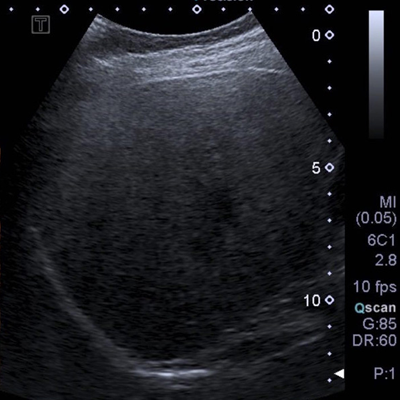

A l’aide d’un produit de contraste spécifique (Sonovue ®) constitué de microbulles très réfléchissantes aux ultrasons ; il est possible d’imager la vascularisation sanguine des organes à des fins diagnostiques, en échographie.

Cet examen fournit une analyse en temps réel de la vascularisation des organes abdominaux, en particulier le foie et les reins.

Il permet dans certains cas précis de caractériser des lésions, d’affiner le diagnostic ou de compléter un dossier pour lequel un doute subsiste.